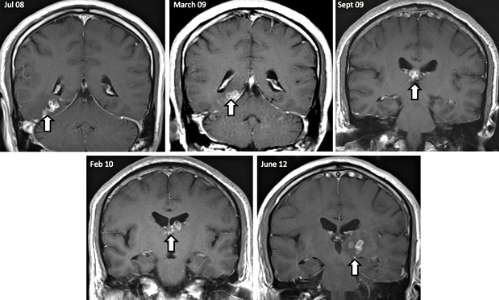

Năm 2013, các bác sĩ ở Anh phát hiện một dạng sán lạ di chuyển

bên trong não bộ của một bệnh nhân. Sau nhiều lần chụp cắt lớp, họ phát hiện ra

vật thể hình tròn kỳ lạ bên trong não của người đàn ông gốc Trung Quốc. Sán đã sống ký sinh

trong đầu của ông trong 4 năm.

"Nó di chuyển từ nửa não bên này sang nửa não bên

kia", bác sĩ Effrossyni Gkrania-Klotsas nói. Đây là dạng sán có thể di chuyển

khắp cơ thể người như mắt, các mô hay phổ biến nhất là não.

Bệnh nhân từng quay về Trung Quốc trong thời gian gần đây. 4 năm

trước đó, ông có những triệu chứng đầu tiên như đau đầu, nhưng được chữa trị

như bệnh lao. Khi quay lại, người này có các triệu chứng mới, khi sán tấn công

vào khu vực khác trong não bộ, gây co giật và đau ở chân. Các biểu hiện đều

liên quan dạng sán dây hiếm gặp có tên khoa học là Spirometra erinaceieuropaei.

Vì chưa có thuốc điều trị hiệu quả, các bác sĩ nhanh chóng phẫu thuật để loại

bỏ chúng.

Ảnh chụp scan cho

thấy sự di chuyển của con sán trong đầu bệnh nhân qua thời gian (mũi tên).

Ảnh: CNN |